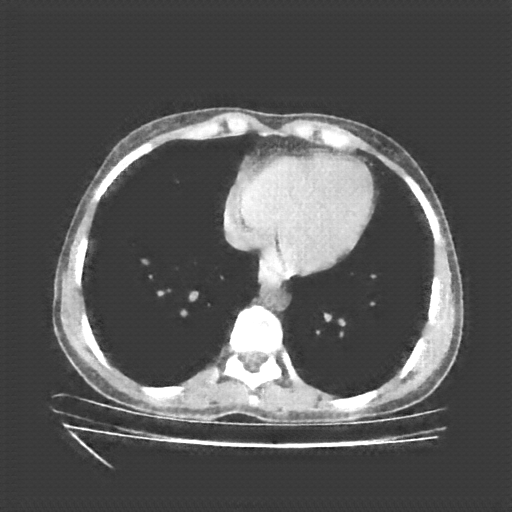

Slice 70 Targeting Evaluation

Slice: Slice_70

Conversion: NATIVE β†’ VENOUS

Image Grid

4Γ—3 grid: Rows show different image types (Original NATIVE, Reconstructed NATIVE, Original VENOUS, Generated VENOUS), Columns show windowing techniques (No Window, Lung Window, Mediastinum Window)

Generated VENOUS CT scan (A→B translation)

No window - Raw intensity values